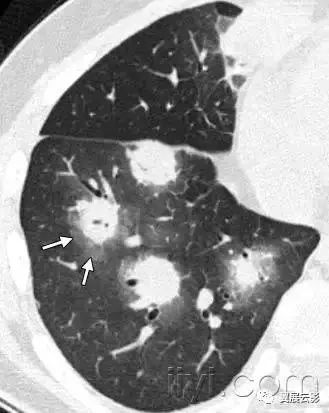

二十四、晕征

CT扫描:晕征是CT上结节或者肿块边缘的磨玻璃影。首先被描述为侵袭性曲菌病边缘的出血征象。实际上晕征是非特异性的,可以见于其它类型结节所致的出血,或者肿瘤的局部肺浸润。(例如腺癌)